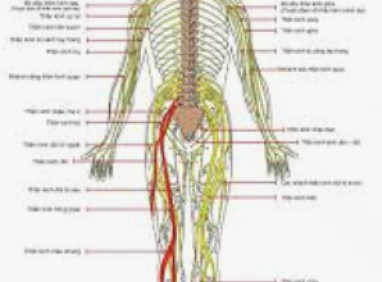

5. Bệnh lý thần kinh hoặc tuần hoàn

Người bị tiểu đường, rối loạn tuần hoàn có thể gặp tình trạng đau rát, tê buốt ở ngón chân, đặc biệt khi thời tiết lạnh.